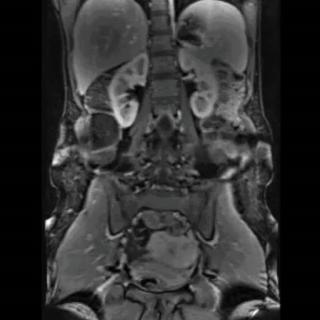

б) Визуализация ангиомиолипомы почки:

• Наиболее распространенное доброкачественное новообразование почки

• В 80% случаев обнаруживают случайно при визуализации

• В 90% случаев-односторонняя и одиночная: обычно не ассоциирована с комплексом туберозного склероза

• В 10% случаев - множественная и двусторонняя: обычно при наличии комплекса туберозного склероза:

о У 80% пациентов с комплексом туберозного склероза обнаруживают ангиомиолипому (АМЛ)

• Солидное гетерогенное образование в коре почки взрослых с макроскопическим жировым компонентом-достоверный признак ангиомиолипомы (АМЛ):

о Может быть выявлено различное количество жира

о 5% всех АМЛ содержат минимальное количество жира и не могут быть распознаны при визуализации

• АМЛ с низким содержанием жира на бесконтрастной КТ часто гиперденсны

(Слева) На рисунке показано сосудистое образование почки с видимыми жировым и мягкотканным компонентами. Обратите внимание на крупные «питающие» артерии. Такая гиперваскуляризация предрасполагает эти опухоли к спонтанным кровотечениям.

(Справа) УЗИ в сагиттальной плоскости: эхогенное образование в коре верхнего полюса левой почки вследствие случайно обнаруженной ангиомиолипоме (АМЛ). Цветовой поток в данном образовании отсутствует. (Слева) КТ без контрастирования, аксиальная проекция: у этого же пациента выявлено образование жировой плотности В в коре верхнего полюса левой почки. Данные признаки характерны для ангиомиолипомы (АМЛ).

(Справа) МРТ, постконтрастное Т1, режим подавления сигнала от жировой ткани, аксиальная проекция: обнаружена ангиомиолипома (АМЛ), которая распространяется в околопочечное пространство. Дефект коры (признак «желобка»), указывающий на происхождение ангиомиолипомы (АМЛ) из ткани почки. Крупный сосуд продолжается в новообразование из почки.